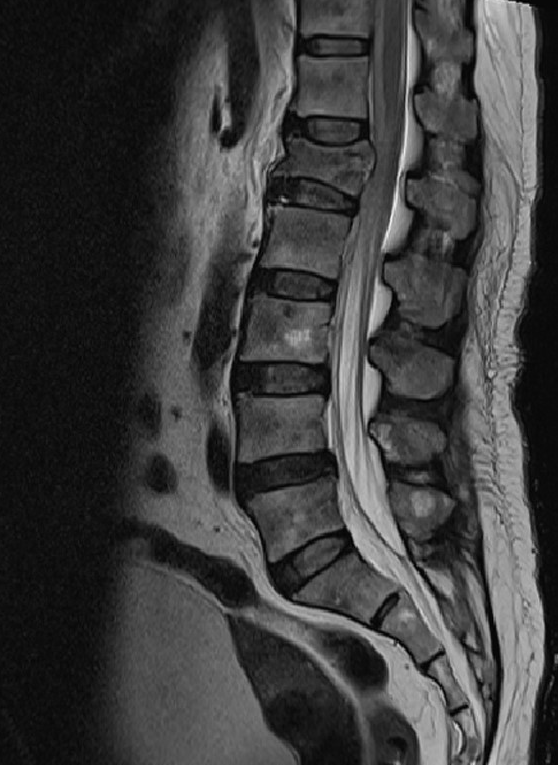

이 사건의 의뢰인은 상대방이 동석한 교통사고 피해자로서 사고 후 요통으로 ○○병원 응급실에 내원하였고 “제2요추폐쇄증후군” 진단을 받았다. 방사선 검사에서 “압박 골절”이 나타났습니다. 부상 초기에 척추의 추가 기형이 진행되거나 신경학적 증상이 나타나면 수술을 준비하고 며칠 동안 경과를 지켜보십시오. 다행스럽게도 통증은 신경학적 증상 없이 차차 가라앉았고, 정형외과를 통한 보존적 치료만이 상당 기간 지속되다가 치료가 종료되었다.

응급실 기록

진단